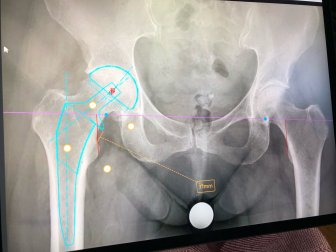

‘Bone-on-bone pain’: B.C. woman pays for private hip surgery in AlbertaA B.C. woman fed up with uncertainty about surgical wait times says she spent more than $34,000 to have her hip replaced at a private clinic in Calgary.HealthOct 16, 2023